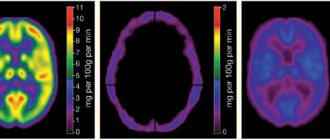

Experts distinguish two types of stroke - ischemic and hemorrhagic. They are radically different from each other, as they have different mechanisms of action and principles of treatment. So, the first type can be called a cerebral infarction in another way. What happens at this moment? The work and patency of the cerebral arteries is disrupted, which leads to prolonged ischemia and changes in brain tissue in the area of ​​​​the blood supply to the affected artery.

Now about all the symptoms in more detail. By general cerebral pain we mean severe headaches, nausea, and often loss of consciousness. Focal signs depend on where in the brain the stroke occurs. If in the carotid artery, then there is a decrease or complete loss of muscle strength in the limbs of one side of the body. Homonymous hemianopsia is also possible, that is, loss of the same halves of the visual fields of both eyes. In some cases, photopsia (false appearance of light flashes, sparks, luminous lines) and visual hallucinations are noted. With a stroke in the vertebrobasilar area (it forms the right and left vertebral arteries that supply the cerebellum, trunk and occipital lobe of the brain), dizziness, diplopia, visual field defects, hearing impairment, oculomotor disorders, dysphagia (inflammation of the oral cavity, pharynx of the esophagus) are noted. Since without medical help it is impossible to understand where exactly the stroke occurred, one should rely on general cerebral signs. Once the diagnosis is made, surgical treatment is necessary.

With occlusion of the central retinal artery (OCAC), obstruction of the central retinal artery or its branches occurs, caused by thrombosis, embolism, or vascular spasm. Spasm manifests itself as vegetative-vascular disorders or organic changes in the vascular wall due to hypertension, atherosclerosis, etc., which is typical, in particular, for older people. In patients with ACAS, systemic diseases are distributed as follows: sclerotic lesions of the cardiovascular system - 35%, hypertension - 25%, heart defects - 8%, temporal arteritis - 3%. And in almost 25% of cases, the cause of CASC is never determined.